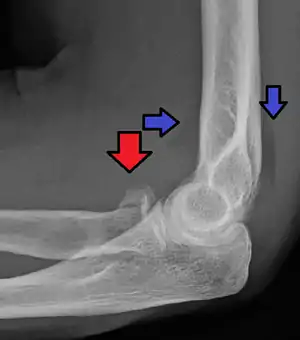

| Radial head fracture (red arrow) with posterior and anterior sail sign (blue arrows) | |